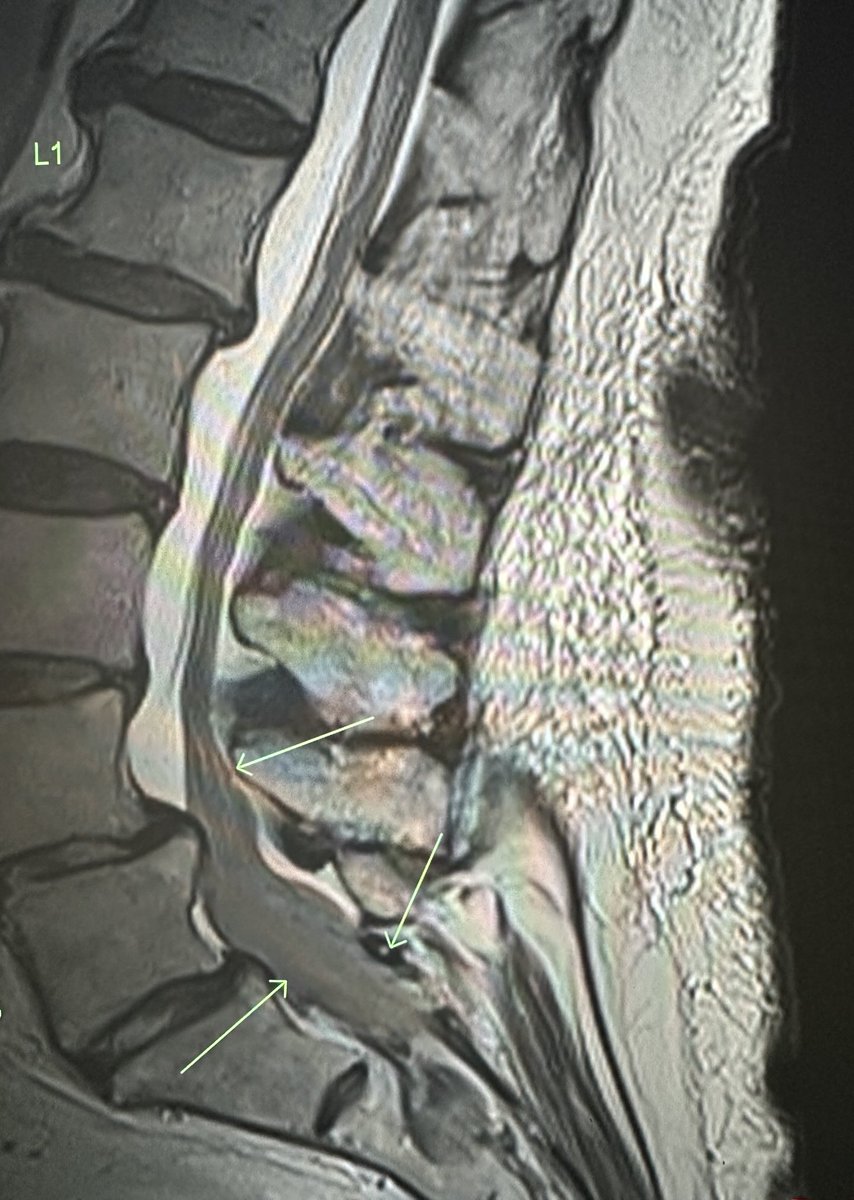

RJ

Elderly female. No interventions. New bilateral lower extremity weakness. Thoughts regarding this finding?

RJ tweet mediaRJ tweet mediaRJ tweet mediaRJ tweet media